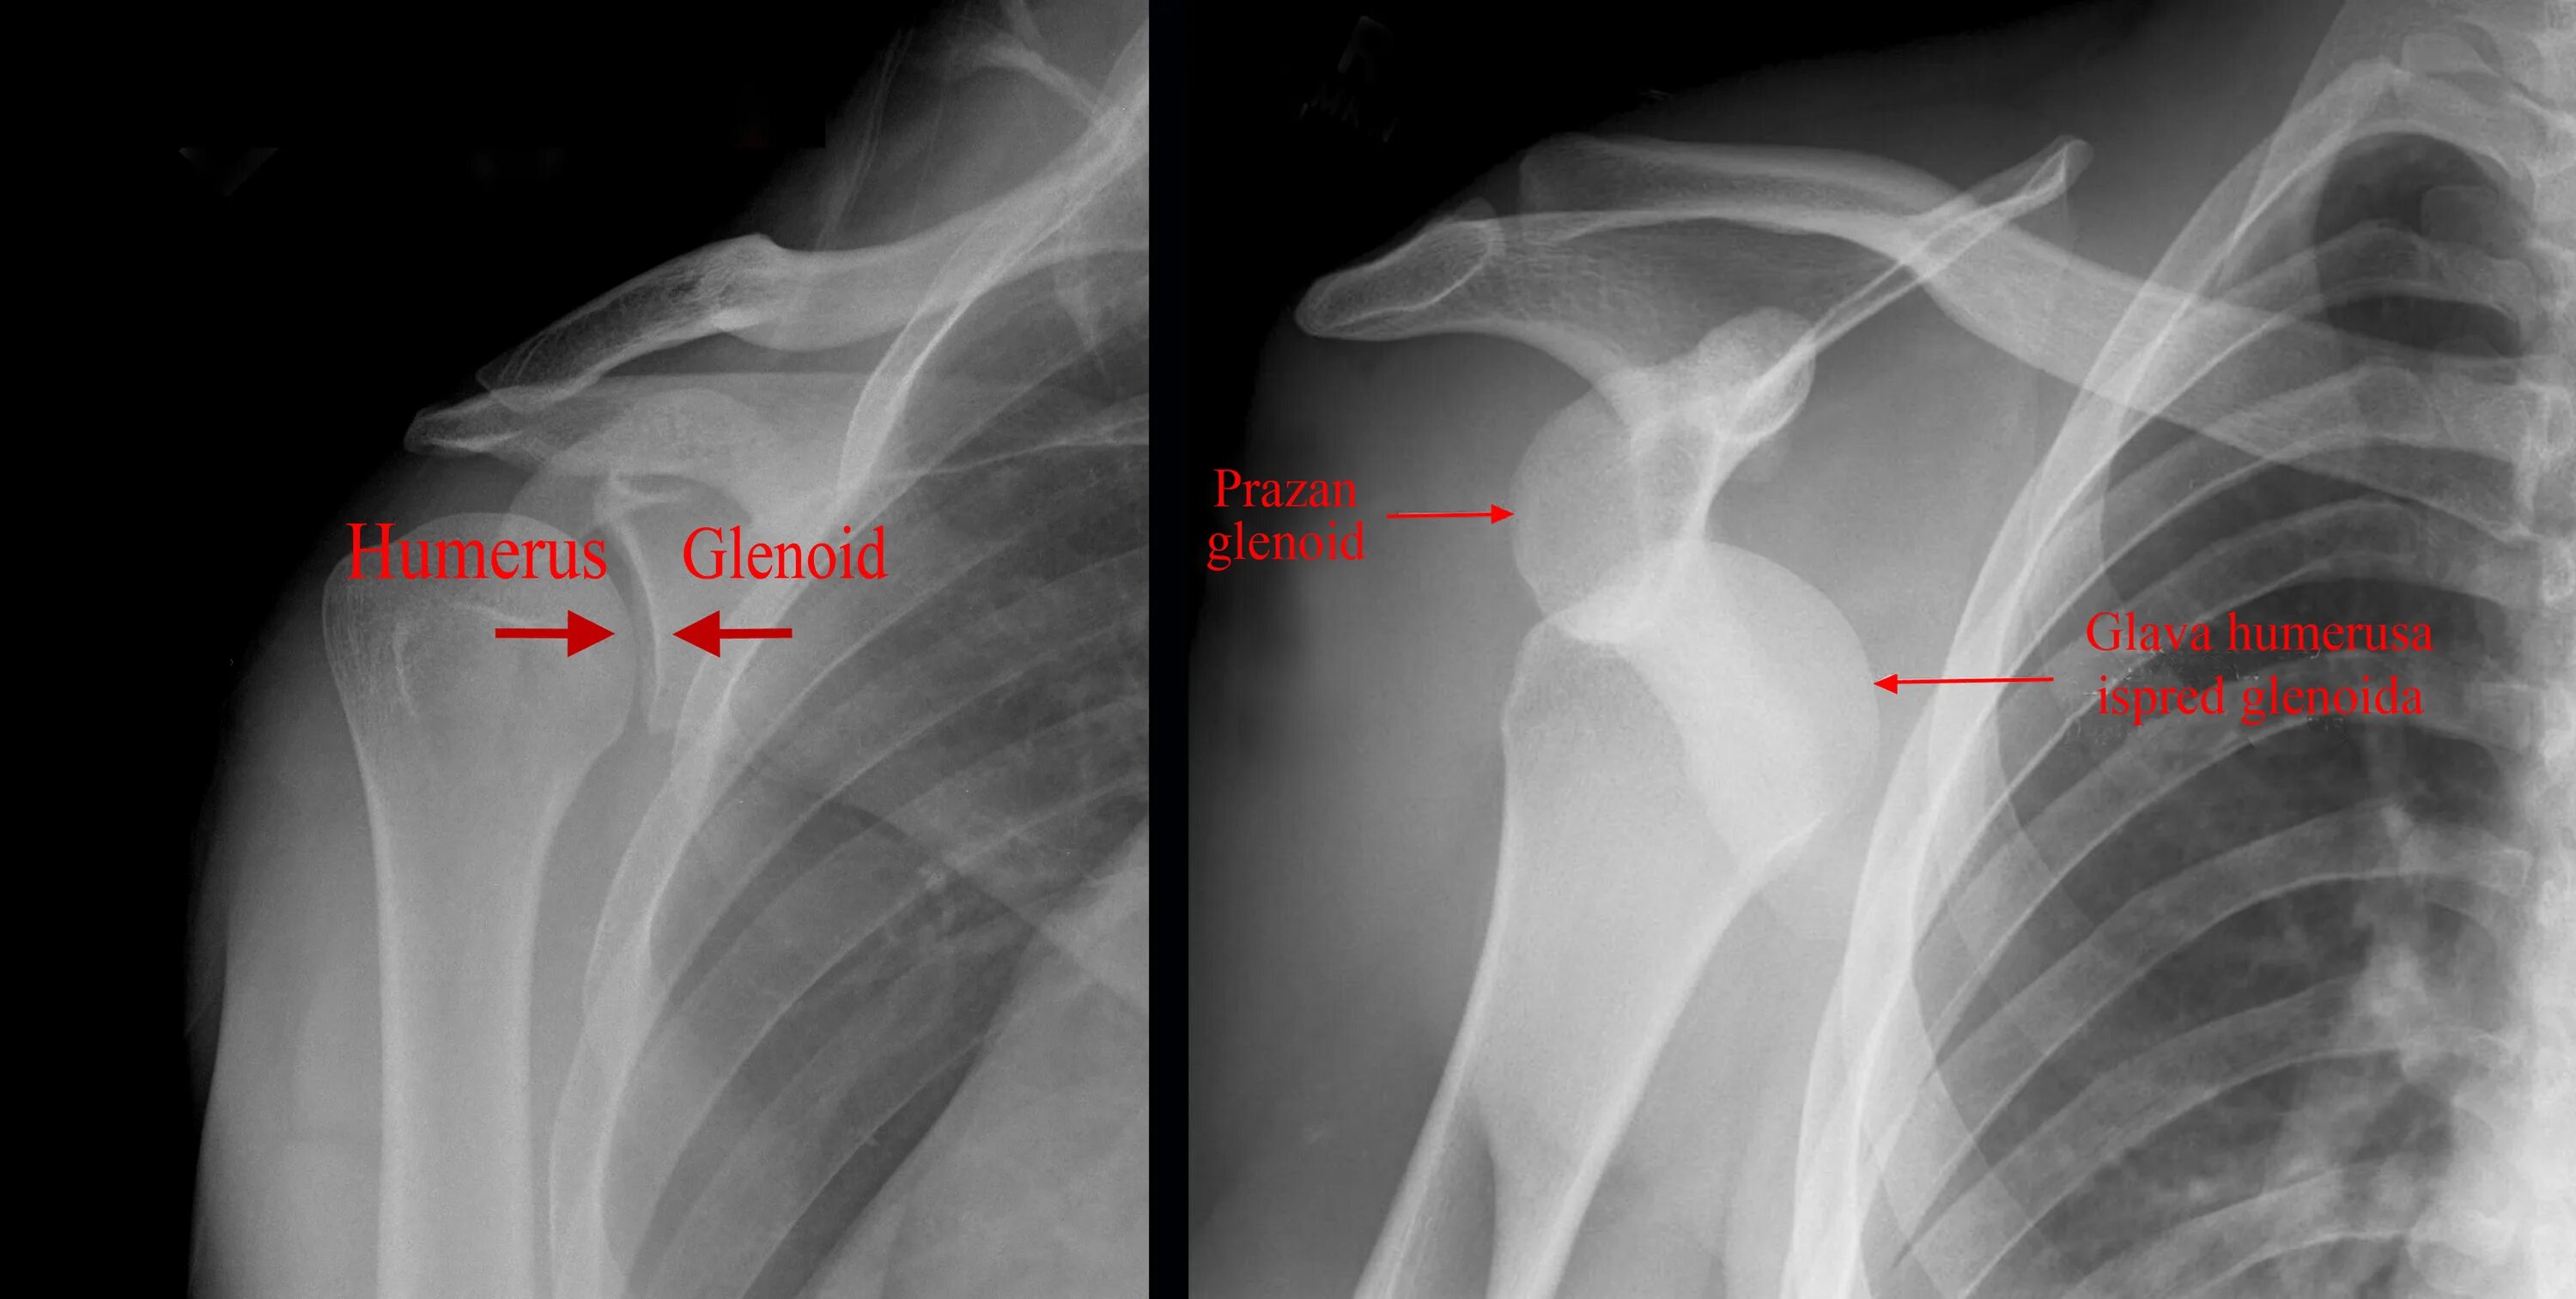

Плечевой сустав у детей